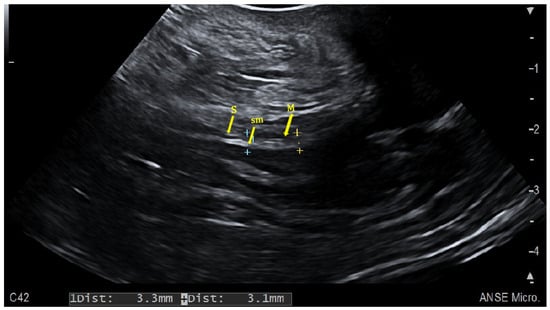

2.1. Colonic Evaluation